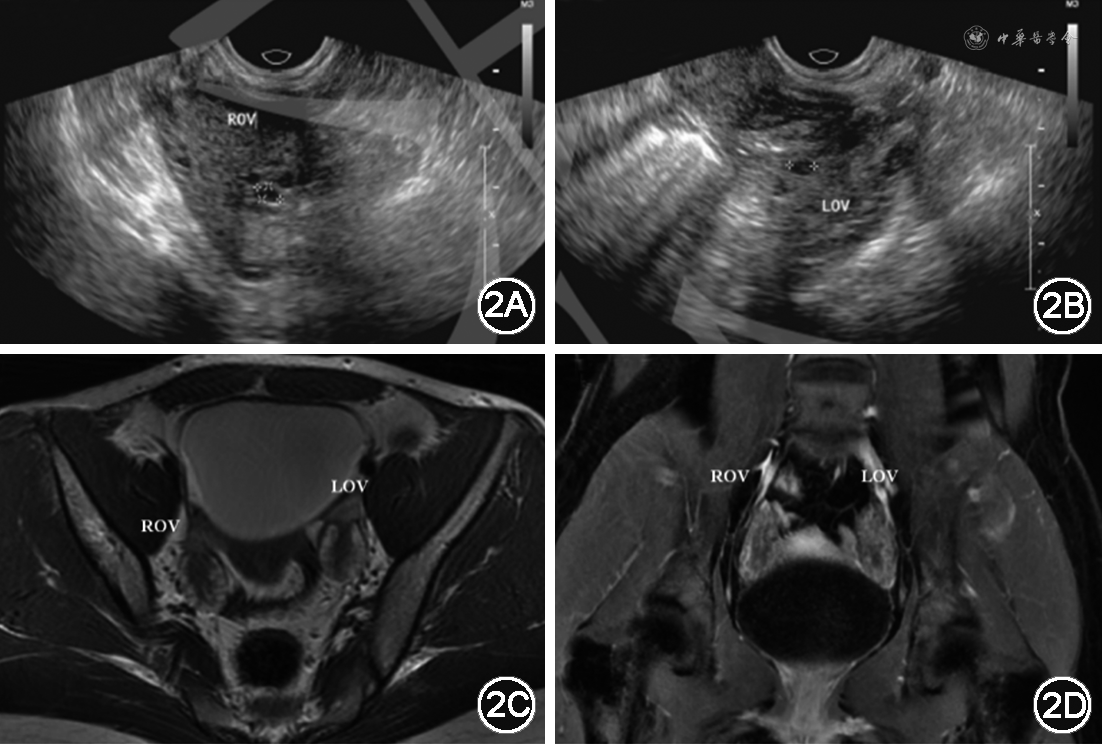

高雄激素血症病因鉴别方面,根据育龄期女性雄激素来源,完善相关鉴别筛查:(1)肾上腺来源:8∶00时促肾上腺皮质激素(ACTH)28.5 ng/L(参考值0~46 ng/L),8:00时血总皮质醇 244 μg/L(参考值40~223 μg/L),0:00时血总皮质醇 17.6 μg/L,24h尿游离皮质醇 63.0 μg(参考值12.3~103.5 μg)。质谱法类固醇激素检测:未见21羟化酶、11β羟化酶等酶底物堆积及下游产物减少情况。中剂量地塞米松抑制试验提示服药后睾酮未被抑制(表1)。肾上腺CT平扫+冠矢状重建未见异常。(2)卵巢来源:子宫及双附件超声(经直肠):子宫内膜约0.3 cm,双侧卵巢体积增大(右侧3.5 cm×3.5 cm×2.9 cm,左侧4.4 cm×2.6 cm×2.2 cm),双侧卵巢小卵泡数目明显增多(数目均大于12个,较大者0.4 cm×0.3 cm),符合双侧多囊卵巢表现,未见明确占位病变(图2)。盆腔增强磁共振成像(MRI)显示:子宫小;双侧卵巢多发小囊泡影,考虑多囊卵巢改变(图2),未见明确卵巢占位性病变。

注:ROV为右侧卵巢;LOV为左侧卵巢